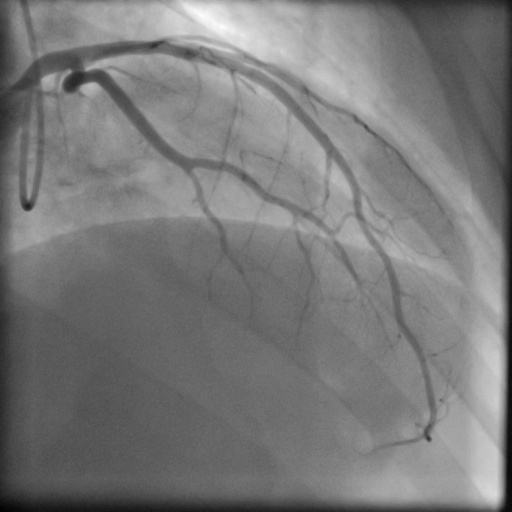

4.1 XACV Dataset

We collect 111 complete records of coronary artery X-ray videos, encompassing the injection, flow through the blood vessels around the heart, and dissipation of the contrast agent. Subsequently, we establish the XACV (X-ray Angiography Coronary Video) dataset. Each video consists of varying numbers of high-resolution coronary artery X-ray images. We invite experienced radiologists to annotate the vascular regions, focusing on one or two frames where the contrast agent is most prominent in each video. The XCAD dataset contains only a single image, and the CADICA video dataset does not provide corresponding ground truth. Therefore, in the following experiments, we conduct all the analyses on our collected XACV dataset and the corresponding GT for each sequence. In Figure 5, we show that compared to other publicly available datasets, XCAD [33] and CADICA [19], our dataset exhibits finer annotations in the vascular regions, providing an advantage for future related tasks. The development and use of our dataset have been approved by our institution’s IRB.